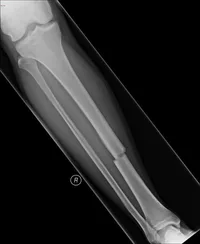

Seorang pria berusia 35 tahun datang ke IGD setelah jatuh dari tangga dengan lengan tertahan dalam posisi ekstensi. Pemeriksaan menunjukkan nyeri hebat di lengan atas dan deformitas pada pertengahan humerus. Apa struktur anatomis yang paling mungkin terlibat dalam fraktur ini?

Humerus